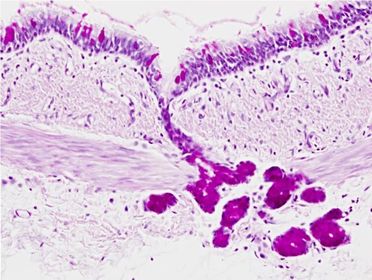

Tejido epitelial: estratificado escamoso (depresiones marcadas)

Tejido epitelial: Pseudoestratíficado (capa densa de núcleos)

Tejido epitelial: Epitelio Glandular